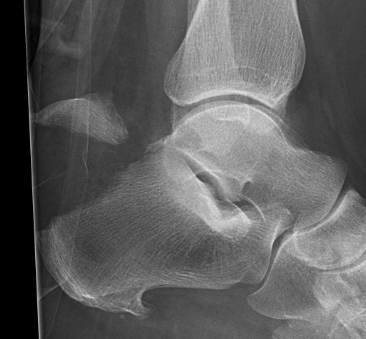

Rockerbottom foot / Persian Slipper Foot

Uncommon

50% bilateral

Doesn't delay walking

- may present in toddler with callus under talus head